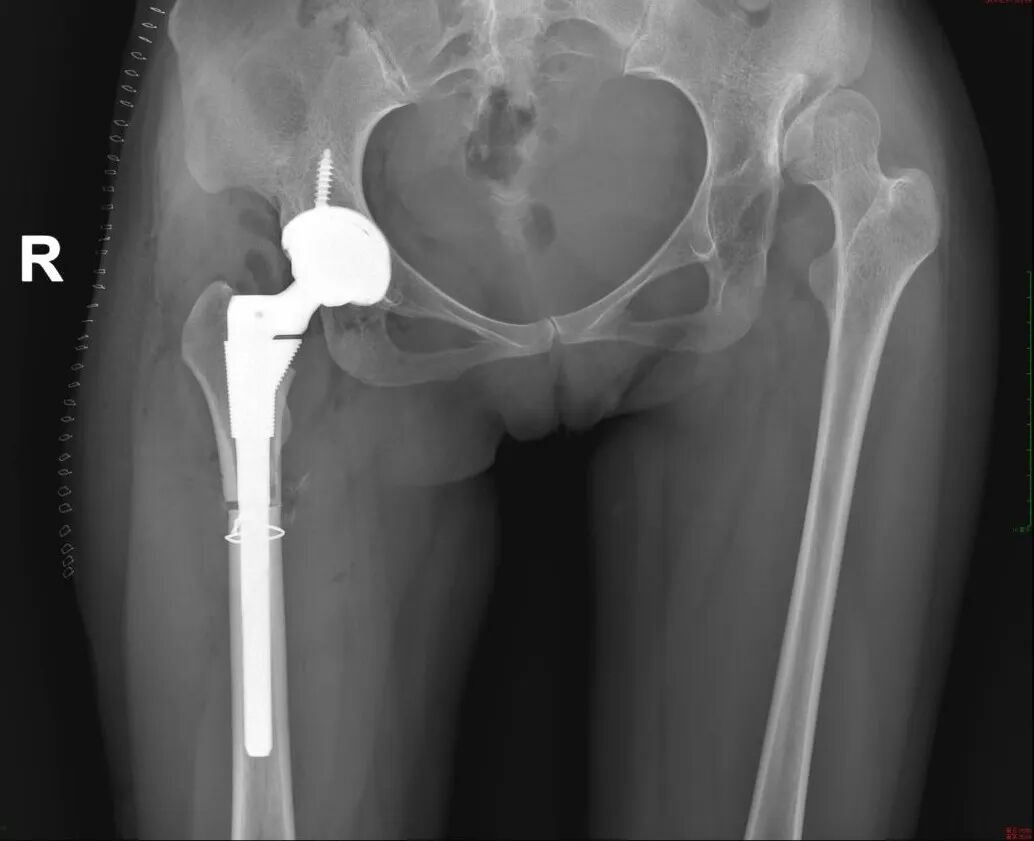

微创置换,告别轮椅生活

36岁的黄梅(化名)已跛行多年,因髋关节发育不良,年幼时期没有及时干预,随着病情的加重,目前已经出现了双侧的髋关节脱位,导致患者走路一高一低,严重影响到患者的学习和生活,给患者带来了诸多的不便和痛苦。

入院2天后,黄梅(化名)被推进了手术室,由于右髋关节脱位严重,北京专家在术中进行了粗隆下截骨,在避免神经损伤的同时,将人工髋关节重建在患者原始的髋关节解剖位置,一场手术短短2个小时,就解决了困扰患者30多年的顽疾。

术后影像

术后第三天,黄梅(化名)缓缓地下床尝试拄拐走路,那种不再跛行的感觉,让她觉得自己就像是破蛹而出的蝶,一切都充满了新鲜和希望。“不用长途奔波,在中山就能得到北京专家的治疗,恢复速度比预期快很多。” 患者家属感激地说。